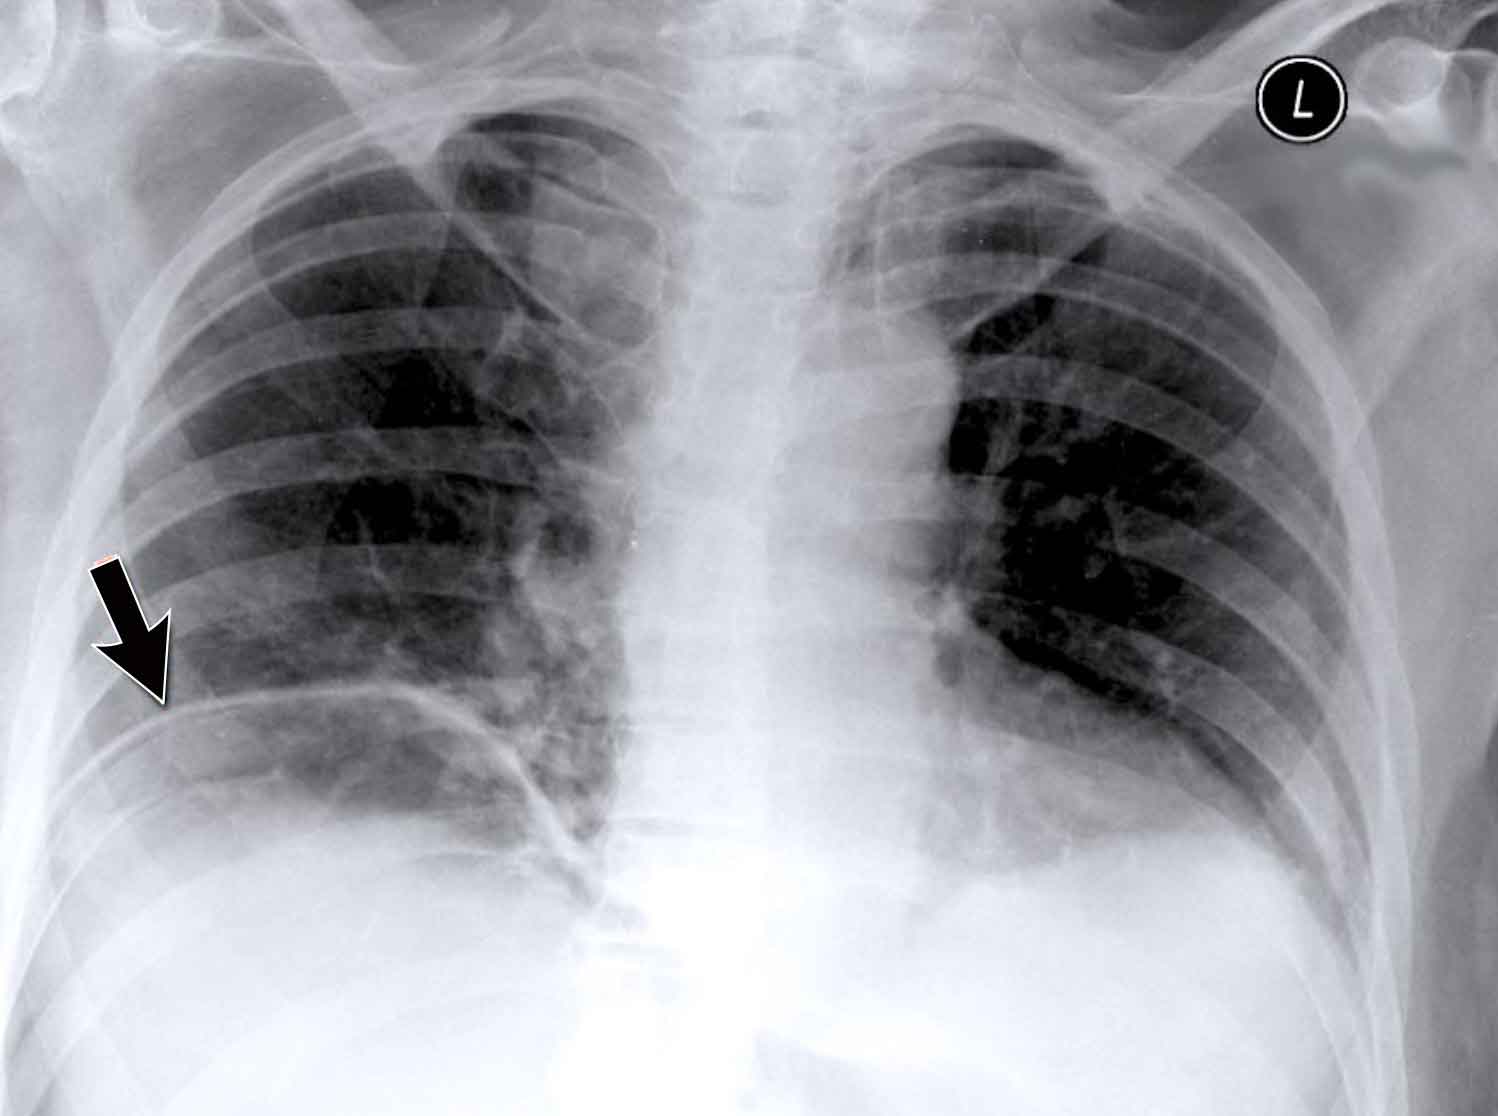

Clinical Case

A 70-year-old male patient presents following a fall down the stairs, complaining of severe right flank pain.

Imaging Findings

• On the PA chest radiograph, there is an absence of the right fifth digit.

• On the lateral view, there is increased density projected over the lower thoracic spine.

What is your diagnosis?

The findings are consistent with right lower lobe atelectasis.

On the PA view, note the abnormal contour of the right heart border. The right interlobar pulmonary artery is not visualized—this is because it is not surrounded by aerated lung, but rather by the collapsed right lower lobe, which lies adjacent to the right atrium.

On follow-up imaging, the right lower lobe has re-expanded, and the atelectasis has resolved.

This suggests that the atelectasis was likely due to post-traumatic hypoventilation with mucus plugging.

Also noted on the follow-up radiograph is the reappearance of the right fifth finger (black arrow), and restoration of a normal right heart border (white arrow), confirming re-expansion of the lower lobe.